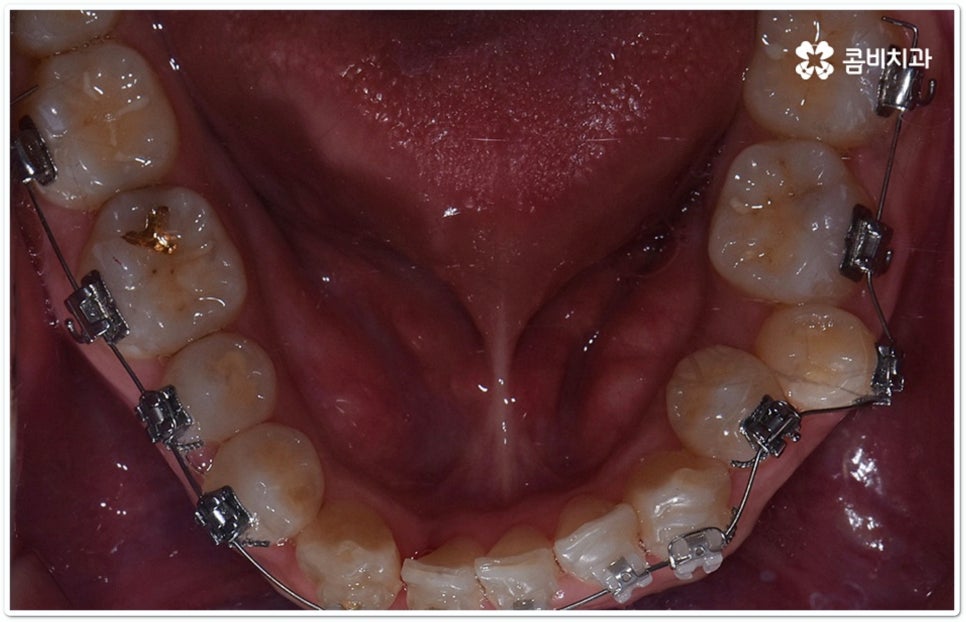

클리피씨교정 장치란 clippy-c 라는 단어 뜻에서 알 수 있듯이 클립이 달린 (clippy) 세라믹(ceramic) 브라켓 장치를 의미하고 있어요. 예전에 교정 장치에서 많이 쓰이던 방식은 고무줄 또는 미세철사를 이용하여 브라켓마다 각각 와이어를 묶어주는 것으로 날카롭게 잘린 철사 끝부분에 자칫 상처를 입을 수도 있고 한 달에 한 번 정도 치과에 내원하여 진행 상황에 따라 교정력을 조정하는 시간도 훨씬 더 많이 걸렸다고 할 수 있습니다.

이와는 다르게 클리피씨교정 장치는 자가결찰방식이라고 해서 각 브라켓에 여닫을 수 있는 특수한 클립(뚜껑)이 달려 있어 전체 와이어를 통과시켜 잡아주는 방식을 이용하기 때문에 겉면이 매끄럽고 진료 시간도 짧아지며 마찰로 빠져나가는 교정력을 줄여주어 좀 더 효율적으로 치아를 이동시킨다고 할 수 있어요. 즉 보다 적은 힘으로 지속적이고 부드러운 치아 이동을 가능하게 하므로 언급했던 것처럼 개인차가 있지만 전체 기간을 약 6개월 정도 단축시키고 치아가 이동할 때 느낄 수 있는 초기 통증도 감소시켜 줄 수 있는 거예요. 또한 치아 색상과 비슷한 세라믹 재질을 이용하기 때문에 음식을 먹거나 대화를 하는 등 입을 벌렸을 때 보일 수 있는 교정 장치가 그렇게 크게 눈에 띄지 않아 심미적으로도 뛰어나다는 장점을 가지고 있습니다.